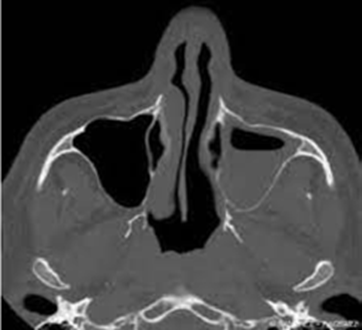

La tomodensitométrie abdominale avec opacification confirmait cette cholécystite avec un foie hétérogène, siège de multiples microlésions arrondies hypodenses, rehaussées légèrement après injection de produit de contraste (Figures 3, 4).